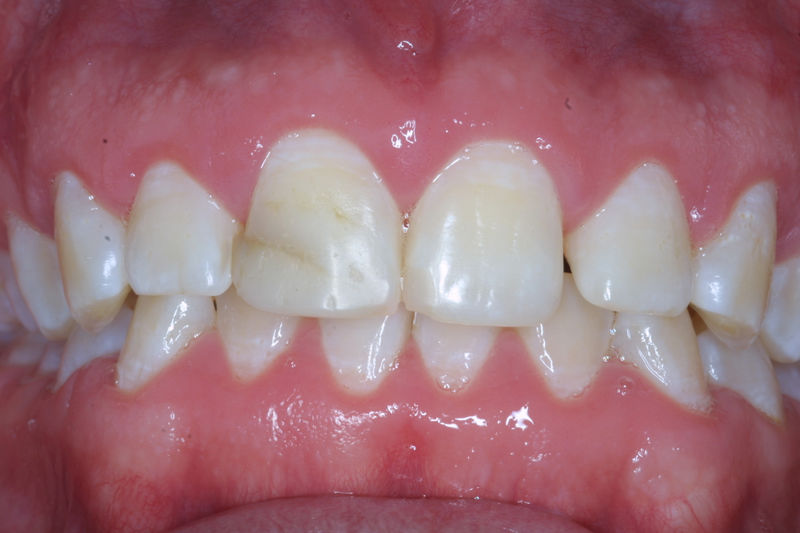

Amplia gama de tratamientos para mejorar la apariencia de la sonrisa, corrigiendo el color, la forma, el tamaño, la alineación y la posición de los dientes. Los procedimientos más comunes y solicitados incluyen el blanqueamiento dental, las carillas y coronas, así como las resinas.

Son restauraciones que cubren toda la cara frontal del diente, generalmente empleadas en el sector anterior y cuya finalidad es primariamente estética.